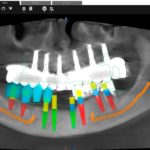

Férulas Guiadas para Implantes

Combinando la Tomografía Computarizada de haz Cónico (CBCT), la informática y el diseño virtual 3D, podemos colocar los implantes de manera totalmente precisa y previsible, mediante guías quirúrgicas de impresión 3D realizadas en el propio centro.

En determinados casos podemos colocar “Dientes en un día”, donde realizamos la extracción de los dientes dañados, la colocación de los implantes y las prótesis en una sola visita, gracias a que aplicamos tecnología de resonancia magnética intraoral para determinar la estabilidad primaria de los implantes que acabamos de colocar.